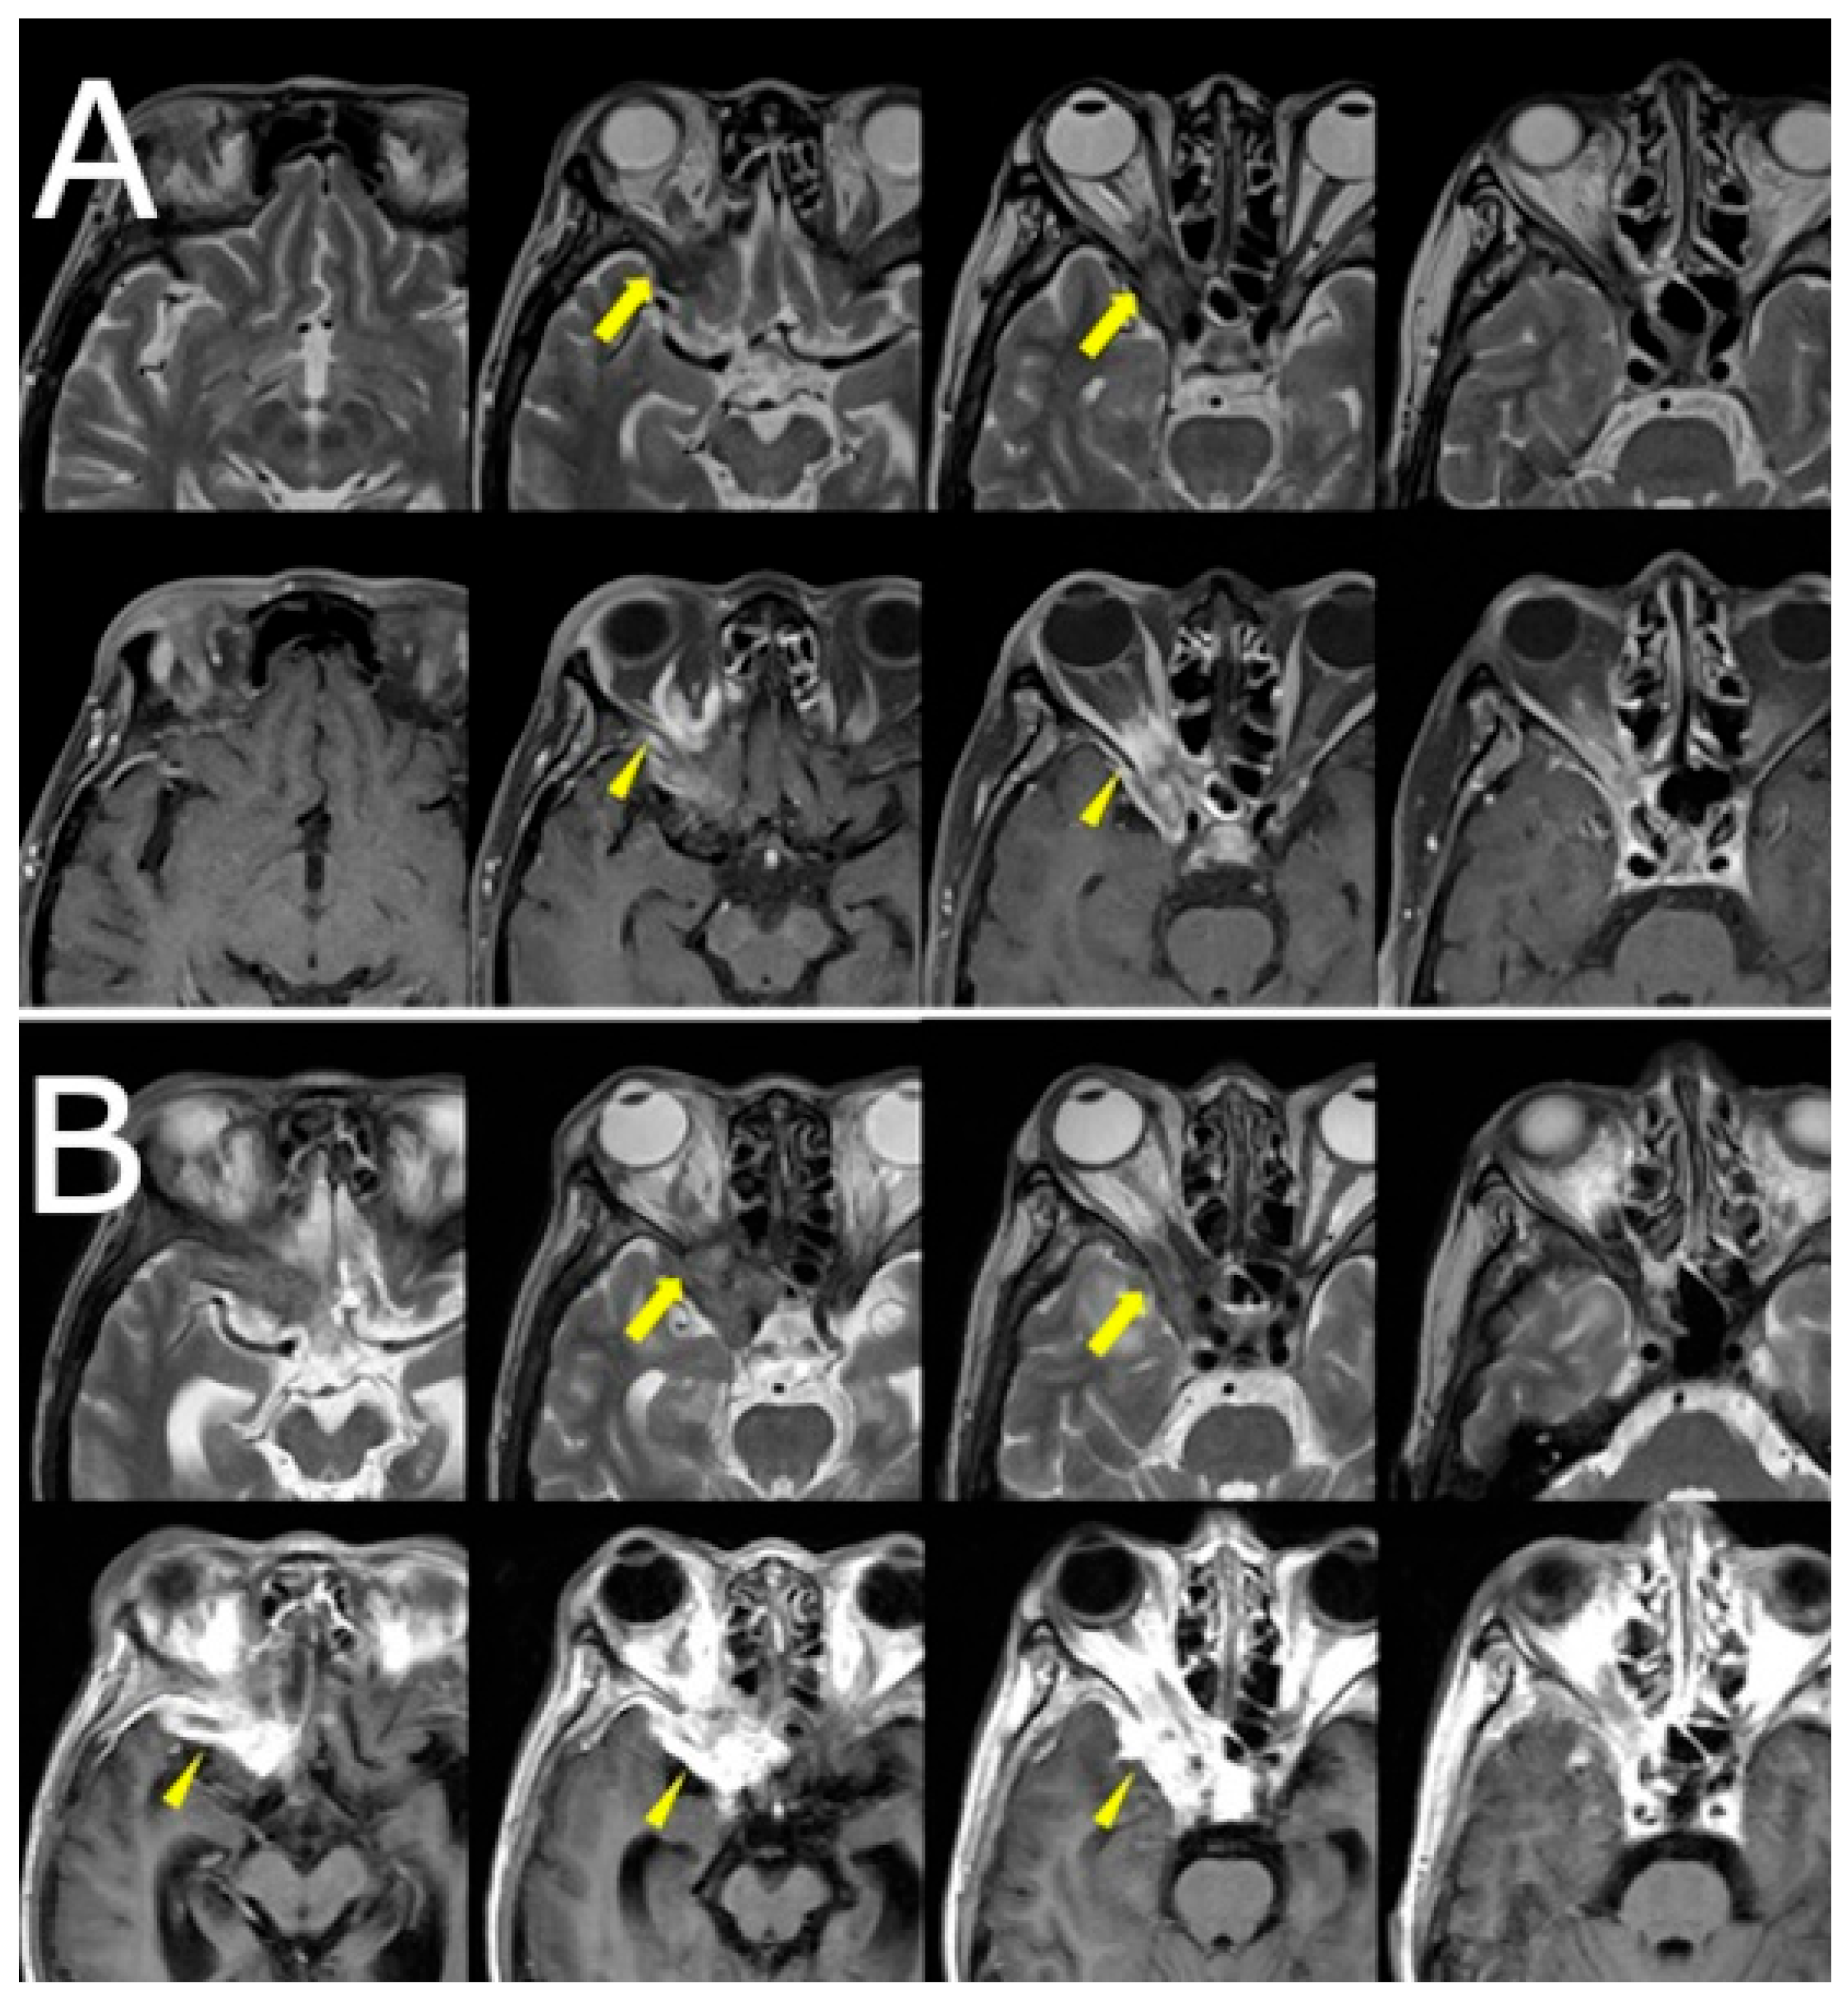

Orbital and brain MRI demonstrated a faint low-signal lesion in the right orbital apex on T2-weighted images, with mild gadolinium enhancement on fat-suppressed T1-weighted images. No surrounding edema or sinus involvement was noted. The lesion was interpreted by the neuroradiologist as likely granulomatous in nature, with a differential that included sarcoidosis and idiopathic orbital inflammation. Given the lesion’s deep location and absence of systemic findings, biopsy was deferred, and clinical observation was initiated (Figure 1A).

Over the following weeks, her symptoms progressed. She reported increasing difficulty in eye movement, blurred vision in the right eye, and worsening retro-orbital pain. Visual acuity in the right eye decreased to 0.3 (20/60), while the left eye remained unaffected. New findings included proptosis and chemosis without conjunctival injection. Repeat MRI revealed lesion progression into the right cavernous sinus and frontal lobe, with peripheral ring enhancement and central diffusion restriction, suggesting abscess formation. Edema in the right frontal lobe was also observed (Figure 1B, Figure 2).

Figure 1. (A) Axial T2-weighted images (top row) and gadolinium-enhanced fat-suppressed T1-weighted images (bottom row) at the initial visit show a subtle low-signal lesion in the right orbital apex (yellow arrows). (B) Follow-up axial T2-weighted images (top row) and gadolinium-enhanced non-fat-suppressed T1-weighted images (bottom row) demonstrate progression of the lesion into the right orbital apex with increased enhancement and slight invasion of the adjacent cavernous sinus (yellow arrows).